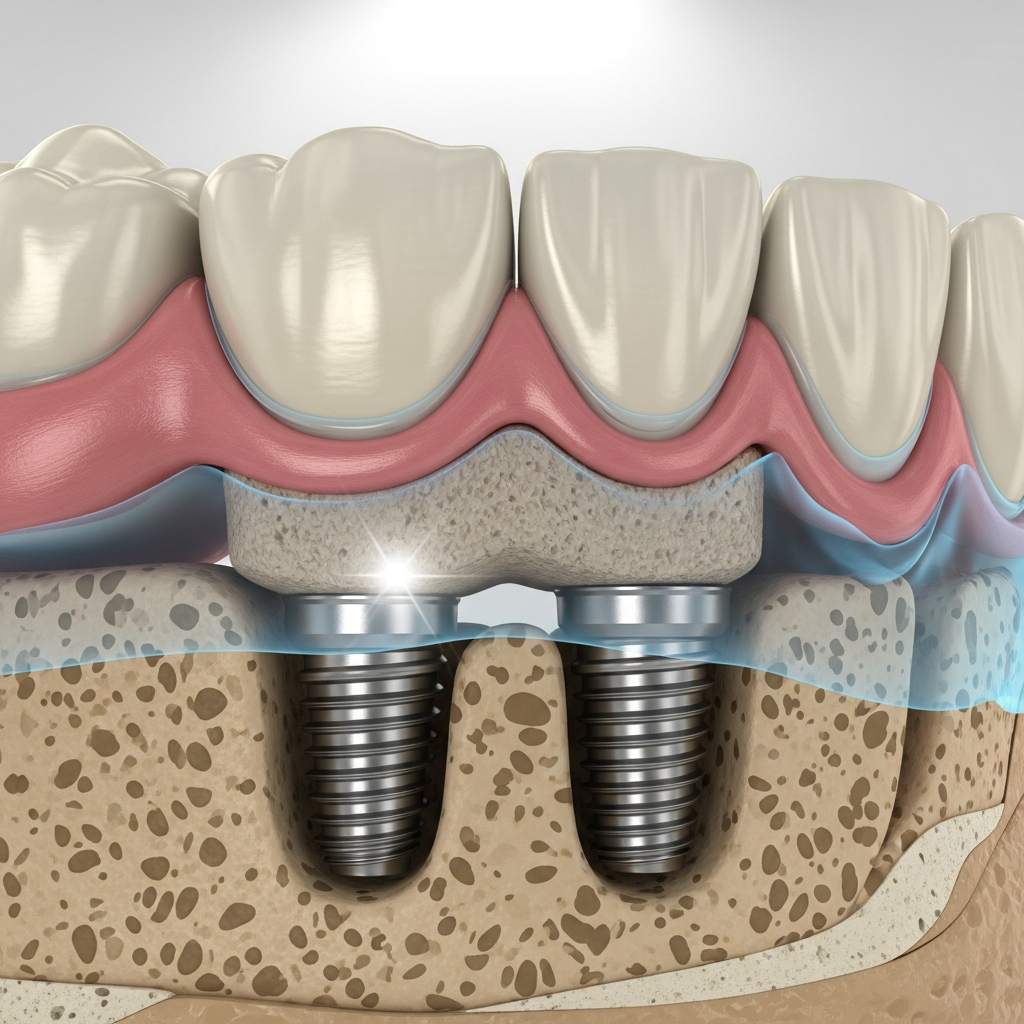

- Design specific: Aceste implanturi sunt adesea monobloc (dintr-o singură piesă), cu o suprafață netedă și filetări laterale, menite să angajeze straturile de os cortical cu densitate mare (osul bazal).

- Ancorare mecanică: Stabilitatea primară nu depinde majoritar de osteointegrarea în osul spongios, ci de blocajul mecanic ferm în două sau mai multe plăci corticale, de unde și denumirea de „bicortical”.

Mecanismul de Stabilitate

Stabilitatea implanturilor bicorticale se bazează pe principiul osteofixării prin inserarea lor în osul cortical rezistent, adesea la nivelul maxilarului superior și inferior. Această fixare robustă minimizează micromișcările și permite transferul forțelor masticatorii direct către structurile osoase dense, contribuind la o predicție bună a succesului pe termen lung, chiar și sub încărcare funcțională precoce.